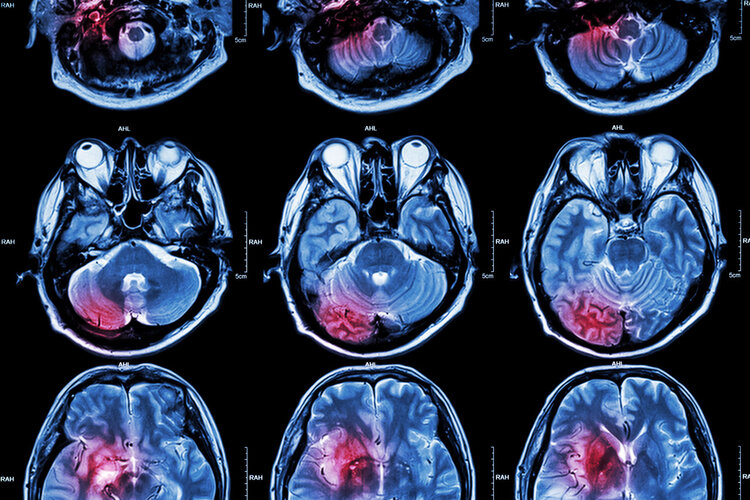

在我国,每年因脑梗而死亡的人数高达200万,这也让很多人对脑梗谈及色变。即便是一些发作后没有引起死亡的人群,再次发病的几率也达到了40%,脑梗的发病率和死亡率一直在攀升,究其原因,主要和2点相关。

当脑梗来临时,身体会有一些异常的征兆,如果你可以及时抓住这些症状,或许可以救你一命。

部分患者在脑梗发生之前会出现血压骤升骤降的情况,一旦发现血压突然升到200/120mmHg或是降到80/50mmHg以下,一定要引起警惕,这可能是脑梗的一个前兆。

3、头晕头痛

大脑供血不足的情况下,患者会出现明显的头晕头痛症状,部分患者还会有眩晕、视物不清、一过性失明的症状,严重影响日常生活。